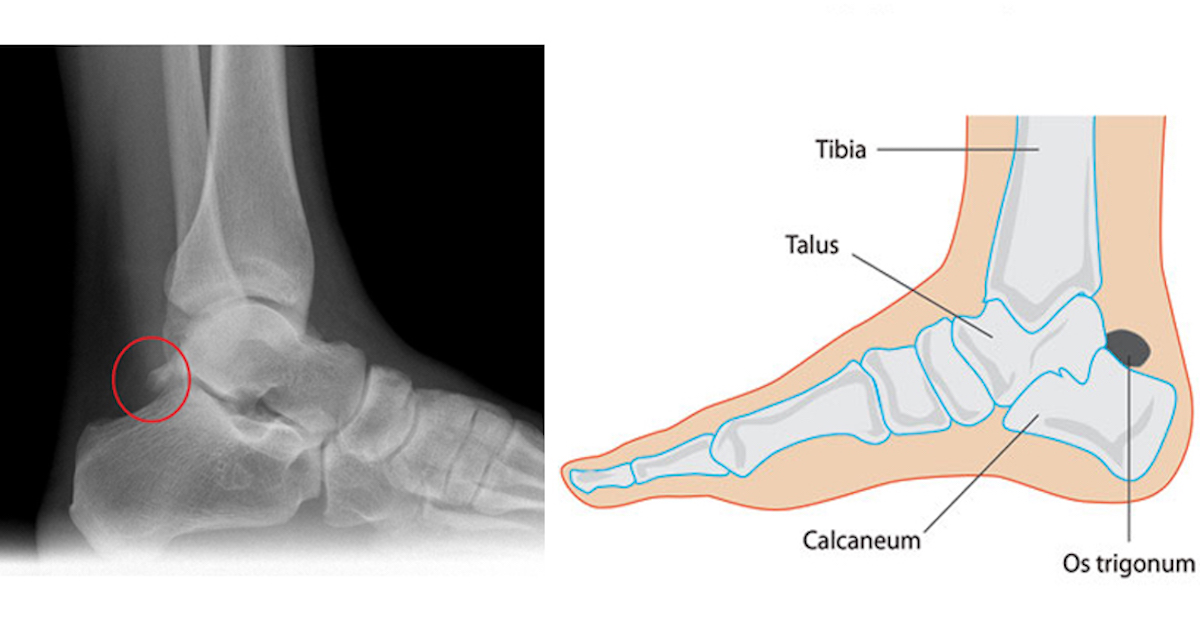

Предплюсна — это часть стопы, расположенная между пяточной костью и передними костями стопы․ Именно здесь сосредоточены основные связки, которые соединяют кости и обеспечивают стабильность всей стопы при движении, ходьбе и беге․ Эти связки позволяют стопе принимать различные формы, поглощать ударные нагрузки и передавать силу при отталкивании․

- Подтаранные связки – соединяют пяточную и кубовидную кости, обеспечивают стабилизацию комплекса суставов в этой области․

| Подтаранная связка | Между пяточной и кубовидной костями | Поддерживает правильное положение сустава и стабилизирует стопу |